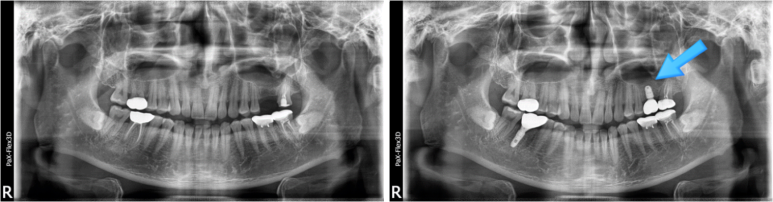

잇몸뼈 부족으로 상악동거상술을 통한 뼈이식 진행한 환자분의 x-ray

일단 수술 자체가 난도가 매우 높고 까다로운 수술인 만큼, 수술에 대한 이해도와 경력이 충분해야 하고요.

또한 환자 얼굴 내부의 해부학적 구조까지 파악하여 수술 계획을 세워야 하는 만큼, 정확한 검사가 가능한 첨단 장비의 역할도 매우 중요합니다.